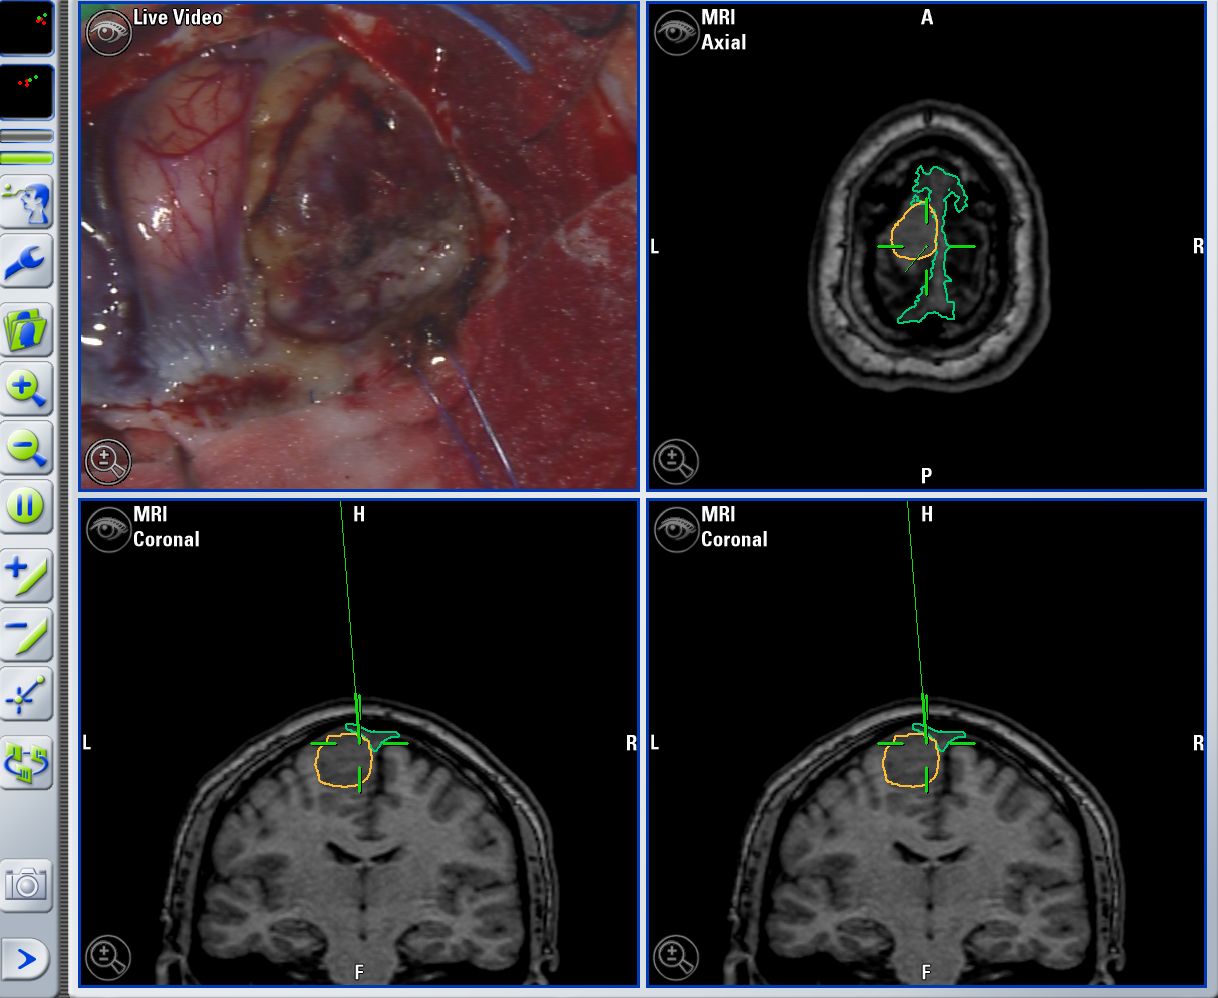

Cirugía de reparación de tumores cerebrales